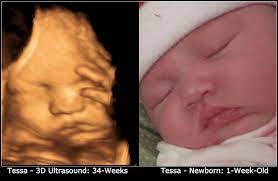

Sweet Baby Face 3d 4d Ultrasound

Sweet Baby Face 3d 4d Ultrasound. Book an appointment in Louisville or Elizabeth today. We Specialize in 4DHD Ultrasound 3D Ultrasound Photography and Baby Boutique items.

We Specialize in 4DHD Ultrasound 3D Ultrasound Photography and Baby Boutique items. Washington Fort Knox Radcliff Shepherdsville Seymour Cincinnati Lexington Elizabethtown Cecilia Corydon Owensboro Indianapolis and Salem. Sweet Baby Face is a 3D 4D Ultrasound and Baby Boutique in Louisville Elizabethtown KY.

Sweet Baby Faces Ultrasound Studio. The entire scanning session video will be provided via email for unlimited sharing with friends and family. 1479 likes 26 talking about this 691 were here. Now you can see your baby up close and personal with a 3D4D HD ultrasound from Sweet Baby Face.